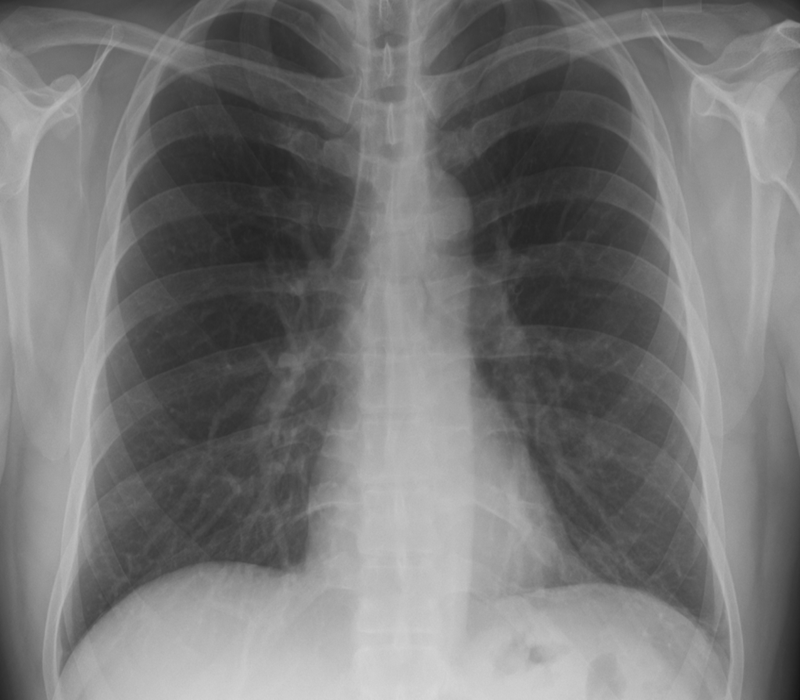

Hastanın vücut yapısı simetrik değildir. Yani vücudun bir yarısıyla diğer yarısı arasında görüntü ve yapı farklılıkları vardır. Özellikle göğüs bölgesinde bulunan yapılarda anormallikler bulunmaktadır. Kişide meme ve meme başı yokluğu da beraberinde görülebilmektedir.

Hastaların göğüs kası olmadığı için bakıldığında simetrik bir görünüm bulunmamaktadır. Estetik bir görüntü olmaması nedeniyle fark edilirler.

Göğüste içbükey bir görünüm vardır. Yine aynı tarafta meme ve meme ucu yokluğu da beraberinde olabilmektedir. Göğüs kaslarına ek olarak kişinin sırt ve kaburgalarında bulunan kasların yokluğu veya burada bulunan kasların liflerinde eksiklik olabilmektedir.

En sık görülen formu meme başının küçük olması ve diğer meme başına oranla daha yukarı seviyede olmasıdır. Bazı hastalarda göğüs duvarında zıt hareket oluşumuna neden olabilecek hasarlı bir göğüs duvarı vardır.

Yani normalde nefes alırken göğüs duvarı genişler ve böylelikle akciğere rahatlıkla hava dolar. Ama burada göğüs duvarı kısıtlama yaptığı için akciğer yeterince genişleyip hava alamaz. Hastada nefes darlığı gibi akciğerle ilgili sıkıntılar görülebilmektedir.